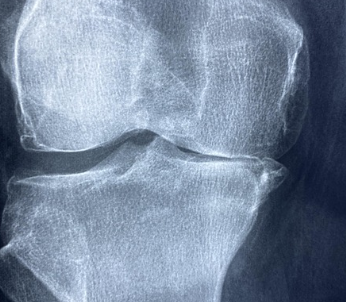

뼈 건강에 도움을 주는 칼슘과 비타민 D

류마치스 관절염 환자는 골다공증 위험도 높아질 수 있습니다. 이때 칼슘과 비타민 D를 챙기면 좋습니다.